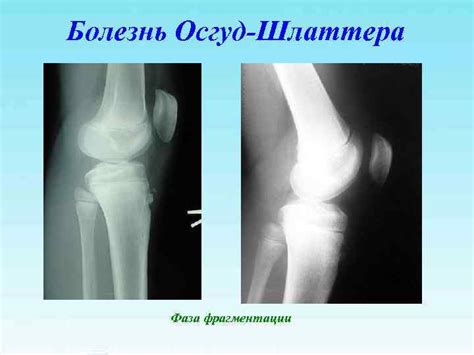

Болезнь Осгуда-Шлаттера

Болезнь Осгуд-Шляттера - презентация онлайн